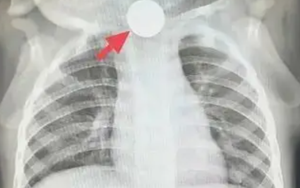

Bé trai 1 tuổi bỏ ăn cả tuần, nguyên nhân được phát hiện khiến bà nội phải thốt lên: “Đúng là lỗi của tôi”

Sống khỏe 2026-01-04T20:04:00Một bé 1 tuổi bỗng nhiên thay đổi tính nết, chán ăn suốt một tuần! Sau khi được bác sĩ ở Thượng Hải thăm khám, nguyên nhân được phát hiện khiến bà nội nhận ra là sơ suất của mình.